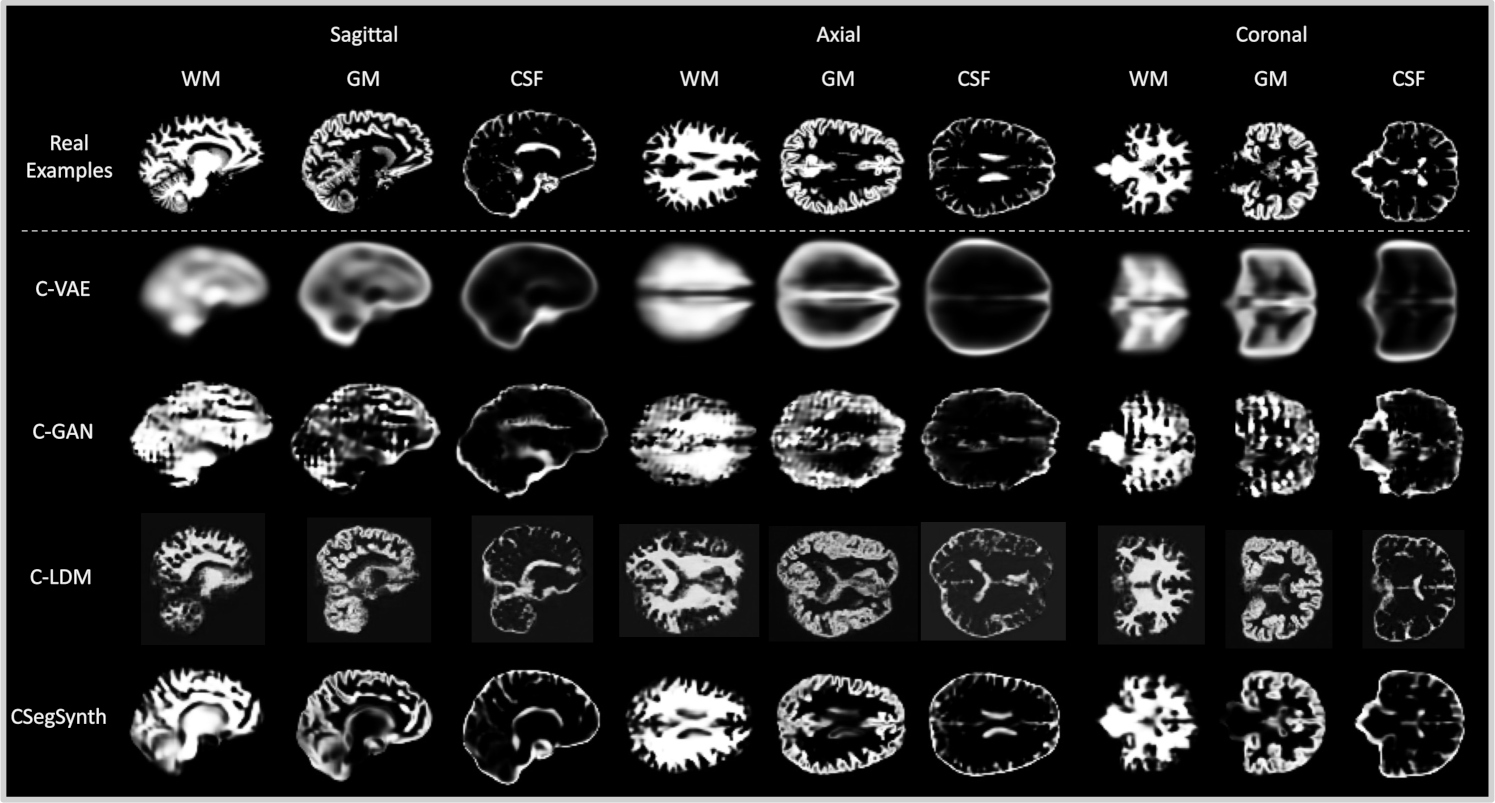

Refer to caption

Figure 2: A comparison of real example segmentations and synthetic segmentations generated by our trained conditional models—C-VAE, C-GAN, C-LDM, and CSegSynth. We present center-cut 2D slices in the sagittal, axial, and coronal views for each 3D segmentation. Please note that, due to CamCAN’s data restrictions, the real examples are sourced from a different public dataset (AOMIC) and are included solely to illustrate the general image quality of real segmentations.

Qualitative Evaluation. Following existing work [7, 30, 23], we randomly select one individual from the CamCAN test set and present synthetic segmentations that our trained conditional models generated for this individual in Fig. 2. We present center-cut 2D slices in the sagittal, axial, and coronal views for clarity. Since CamCAN is not a public dataset, we cannot show the individual’s real segmentations for direct comparison. Nevertheless, as our goal in this evaluation is to assess the overall image quality, we include visually similar real example segmentations from the publicly available AOMIC dataset in Fig. 2 for reference. We summarize our main findings in the following. Notably, these findings are not specific to the presented individual but generalize across the entire test set.

• C-VAE is only able to capture the overall shape of WM, GM, and CSF. Its synthetic segmentations appear substantially blurrier than those of the other models. This is an inherent limitation of C-VAE and has been also widely observed in other image generation tasks [19].

• The blurriness issue of C-VAE can often be mitigated by replacing the voxel-wise reconstruction loss with the generator-discriminator mini-max loss of C-GAN. However, the training of C-GAN is challenging and prone to instability [19], particularly in our task, where the training data is significantly limited. Consequently, in Fig. 2, we observe substantial unnatural artifacts in the synthetic segmentations of C-GAN.

• As a state-of-the-art deep generative model, C-LDM generates segmentations with superior fidelity compared to C-VAE and C-GAN. However, we find that C-LDM is prone to distortions and inconsistencies. As observed in the axial view of its generated segmentations, the synthetic left and right cerebral hemispheres appear abnormally asymmetric. Similar substantial distortions are also evident in the sagittal view.

• CSegSynth jointly utilizes the reconstruction loss of C-VAE and the generator-discriminator mini-max loss of C-GAN. It achieves superior fidelity compared to C-VAE and C-GAN. Moreover, compared to C-LDM, CSegSynth exhibits stronger robustness against distortions. Most importantly, CSegSynth demonstrates the strongest ability among all trained models in capturing detailed brain structures, as evidenced by more realistic cerebral ventricles and cortical gyri in the synthetic segmentations.